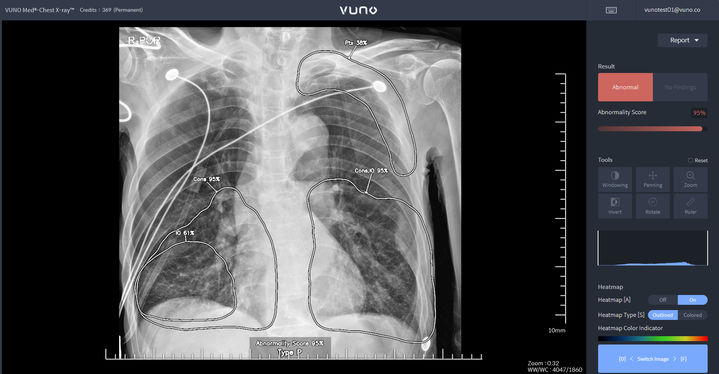

[서울=뉴시스] 뷰노는 자사가 개발한 흉부 영상 진단 보조 인공지능(AI)이 내달 1일부터 비급여 시장 진입이 가능해졌다고 15일 밝혔다. (사진=뷰노 제공) 2025.05.15. [email protected] *재판매 및 DB 금지

인공지능(AI) 기업 뷰노는 AI 기반 흉부 X-ray 판독 및 소견 검출 의료기기 '뷰노 메드 체스트 엑스레이'가 지난 1월 혁신의료기기 통합심사·평가에서 승인을 받은데 이어, 이달 보건복지부의 혁신의료기술 관련 고시가 확정됐다며 15일 이같이 밝혔다.

뷰노의 체스트-엑스레이는 안전성과 진료 현장에서의 잠재적 유용성을 인정받은 의료 AI 솔루션으로, 이번 고시에 따라 내달 1일부터 오는 2028년 5월 31일까지 3년간 임상 현장에서 사용이 가능해졌다. 해당 제품은 흉부 X-ray 영상을 분석해 5개의 이상 소견(결절, 경화, 간질성 음영, 흉막 삼출, 기흉) 유무를 검출하고 소견 조합을 통해 2개 질환(폐렴, 폐결핵)을 선별하는 진단 보조 소프트웨어이다.